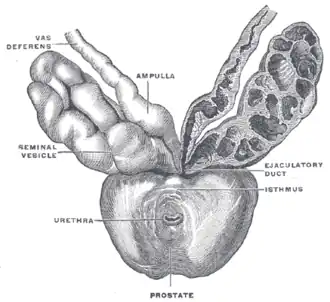

Die Prostata liegt subperitoneal, das heißt unter (bei Tieren entsprechend hinter) dem Bauchfell. Sie ruht auf dem Diaphragma urogenitale und schmiegt sich von kaudal (beim Menschen unten, bei Vierfüßern hinten) an den Hals der Harnblase an. Dorsal (zum Rücken hin) wird sie durch den Mastdarm begrenzt, ventral (zum Bauch hin) durch die Schambeinfuge. Mit dieser ist sie durch ein Band, das Ligamentum puboprostaticum, verbunden. Durch die Mitte der Prostata verläuft die Harnröhre. Aus diesem Grund kann es bei einer krankhaften Vergrößerung der Prostata zu Problemen beim Wasserlassen bis hin zum Blasenverschluss kommen.

Anatomisch lässt sich die Prostata in einen rechten, linken und mittleren Lappen untergliedern: Lobus prostatae dexter, Lobus prostatae sinister und Isthmus prostatae (Lobus medius). Die funktionelle Gliederung in Zonen nach McNeal unterscheidet die periurethrale Zone (um die Harnröhre herum), die Transitionalzone (Übergangszone), die zentrale Prostatazone (Innenzone), die periphere Prostatazone (Außenzone) und die drüsenfreie vordere Prostatazone.[1]

Durch die Prostata verläuft beim Menschen außerdem der paarig angelegte Spritzkanal (lat. Ductus ejaculatorius), durch den während der Ejakulation ca. 70 % des Ejakulat-Volumens hindurchfließen, nämlich die Fraktionen aus dem gleichseitigen Nebenhoden und aus der gleichseitigen Bläschendrüse.[2]

Die Ausführungsgänge der Prostata münden seitlich des Samenhügels in den Beckenteil der Harnröhre.